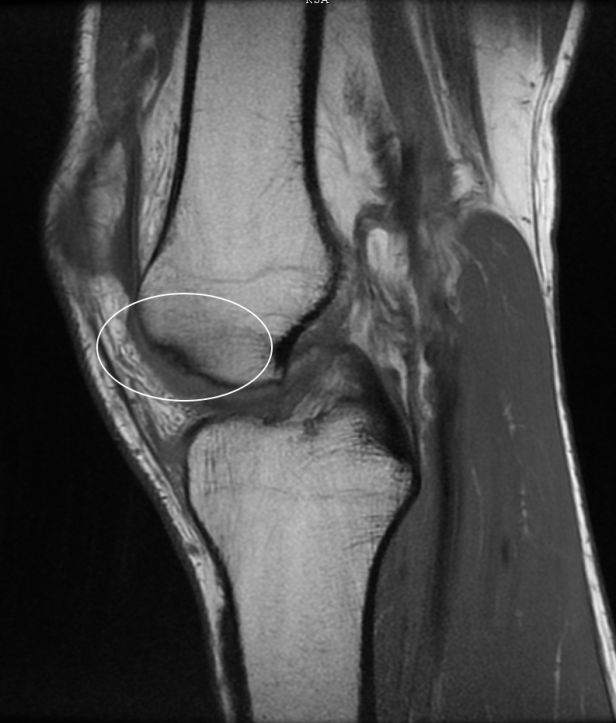

The consultant, the exceptional Fiona Middleton at Clare Park Hospital, put me straight. No running for a while, but bike, swim and race….back on. Don’t expect a decent time (as if) and don’t go crazy but you can get back on. No op needed. It’s worth keeping an eye on the bone ‘fronds’ (see below) and there’s the potential for an operation to smooth it off, but in her words, I’ll end up with a shorter leg which could cause all sorts of other problems. I did mention they could trim my other leg but we agreed we may end up turning me into a modern day Jimmy Krankie and nobody wants that.

For those interested in science, the below is a collection of the grabs from the MRI with my understanding. Bear in mind I’m not a doctor, so take it with a pinch of sodium replacement. See you in Wales, Tenby had better have streets lined with feathers or it might hurt a bit!

- I have a pitted surface on the base of the femur which combined with increased pressures on the knee has allowed the honeycomb of the bone to fill with fluid. Like a bone bruise.

- All meniscus present and correct, some lack of cartilage but nothing terrible.

- Fluid on the back of the hamstring and down to the joint, stretching. Some thing that I’ve never really done. I may have the odd roll on some foam rollers but I don’t have a regime.

Here comes the science